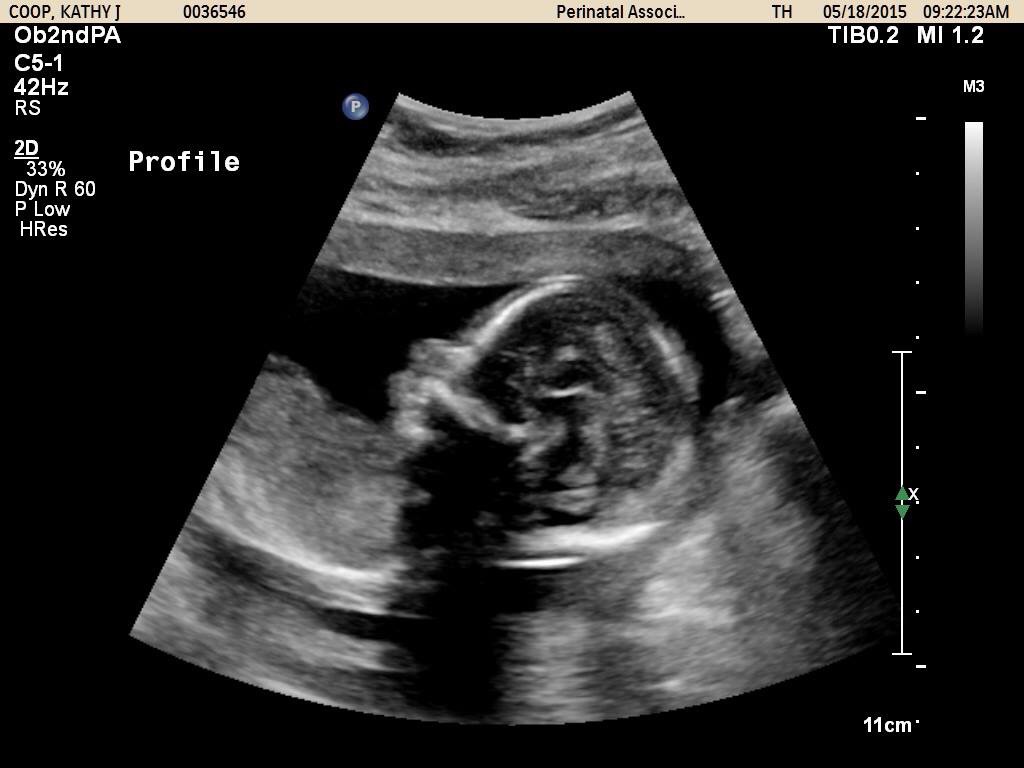

Anatomy Ultrasound Pics!